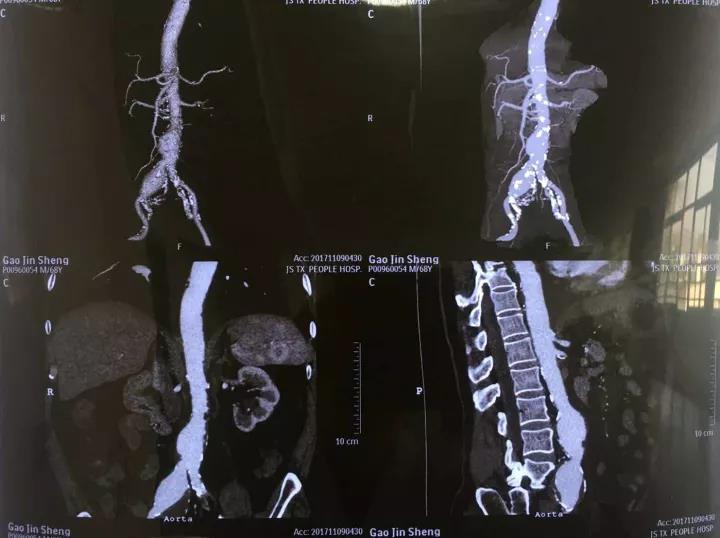

患者高某今年68歲,于4月前去外地治療時(shí)發(fā)現(xiàn)腹主動(dòng)脈瘤。后瘤體不斷增大,至入住我院經(jīng)CT檢查時(shí)瘤體直徑已近5厘米。

12月6日,患者被送入介入手術(shù)室,醫(yī)護(hù)人員同時(shí)以最快速度做好術(shù)前準(zhǔn)備。介入室中,手術(shù)團(tuán)隊(duì)根據(jù)DSA造影再次明確診斷及病變的手術(shù)指征,迅速對(duì)瘤體做出評(píng)估與測(cè)量,討論并確定了腹主動(dòng)脈瘤覆膜支架植入腔內(nèi)隔絕術(shù)的詳細(xì)手術(shù)方案。手術(shù)團(tuán)隊(duì)經(jīng)患者大腿股動(dòng)脈植入覆膜支架,將動(dòng)脈瘤腔隔絕后重建新的腹主動(dòng)脈腔血流通道。原動(dòng)脈瘤腔因無(wú)血流沖擊,瘤壁壓力得到解除,從而避免了瘤體的破裂。